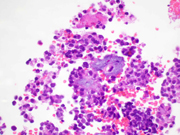

• Figure 1: FNA material, smear, Diff-Quick stain, 40x magnification

• Figure 2: FNA material, smear, Pap stain, 60x magnification

SPN is a low-grade malignant pancreatic tumor composed of poorly cohesive epithelioid to plasmacytoid cells forming solid and pseudopapillary structures. The definitive cell of origin remains unclear. These tumor cells appear bland and uniform with a moderate amount of cytoplasm, which contains clear perinuclear vacuoles and/or hyaline globules. Nuclei are round to oval with grooves and finely granular chromatin.